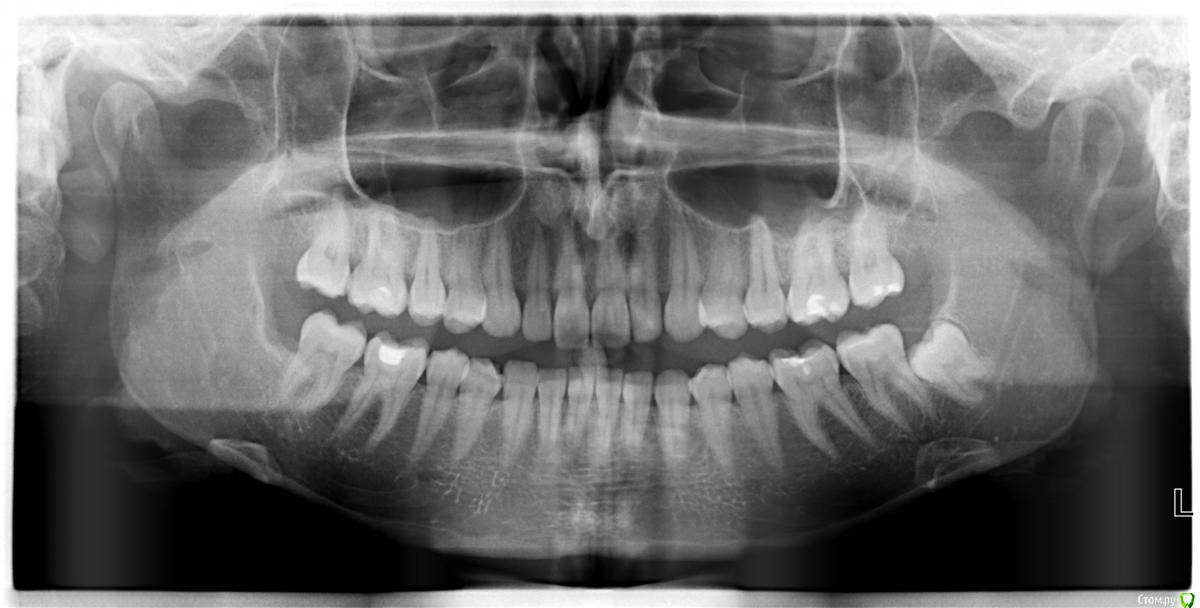

Tatyanka Опубликовано 9 марта, 2015 Автор Поделиться Опубликовано 9 марта, 2015 И снова здравствуйте! Все же доктор решил, что удаление было травматичным, т.к. 6, 7 и остальные зубы опасений не вызвали. В процессе лечения сразу стало легче, но даже сейчас, через 3 месяца после удаления, иногда беспокоит терпимая ноющая боль в районе 6, 7 и лунки 8. Удалось сделать ОПТГ - можете что-нибудь подсказать по снимку? Ссылка на комментарий

shishok Опубликовано 9 марта, 2015 Поделиться Опубликовано 9 марта, 2015 Заживает хорошо. Ссылка на комментарий

St. Опубликовано 9 марта, 2015 Поделиться Опубликовано 9 марта, 2015 стало легче, но даже сейчас, через 3 месяца после удаления, иногда беспокоит терпимая ноющая боль в районе 6, 7 и лунки 8. Удалось сделать ОПТГ - можете что-нибудь подсказать по снимку?По снимку всё неплохо. Не переживайте! Скорее всего все неприятные ощущения постепенно пройдут, просто нужно время. Ссылка на комментарий